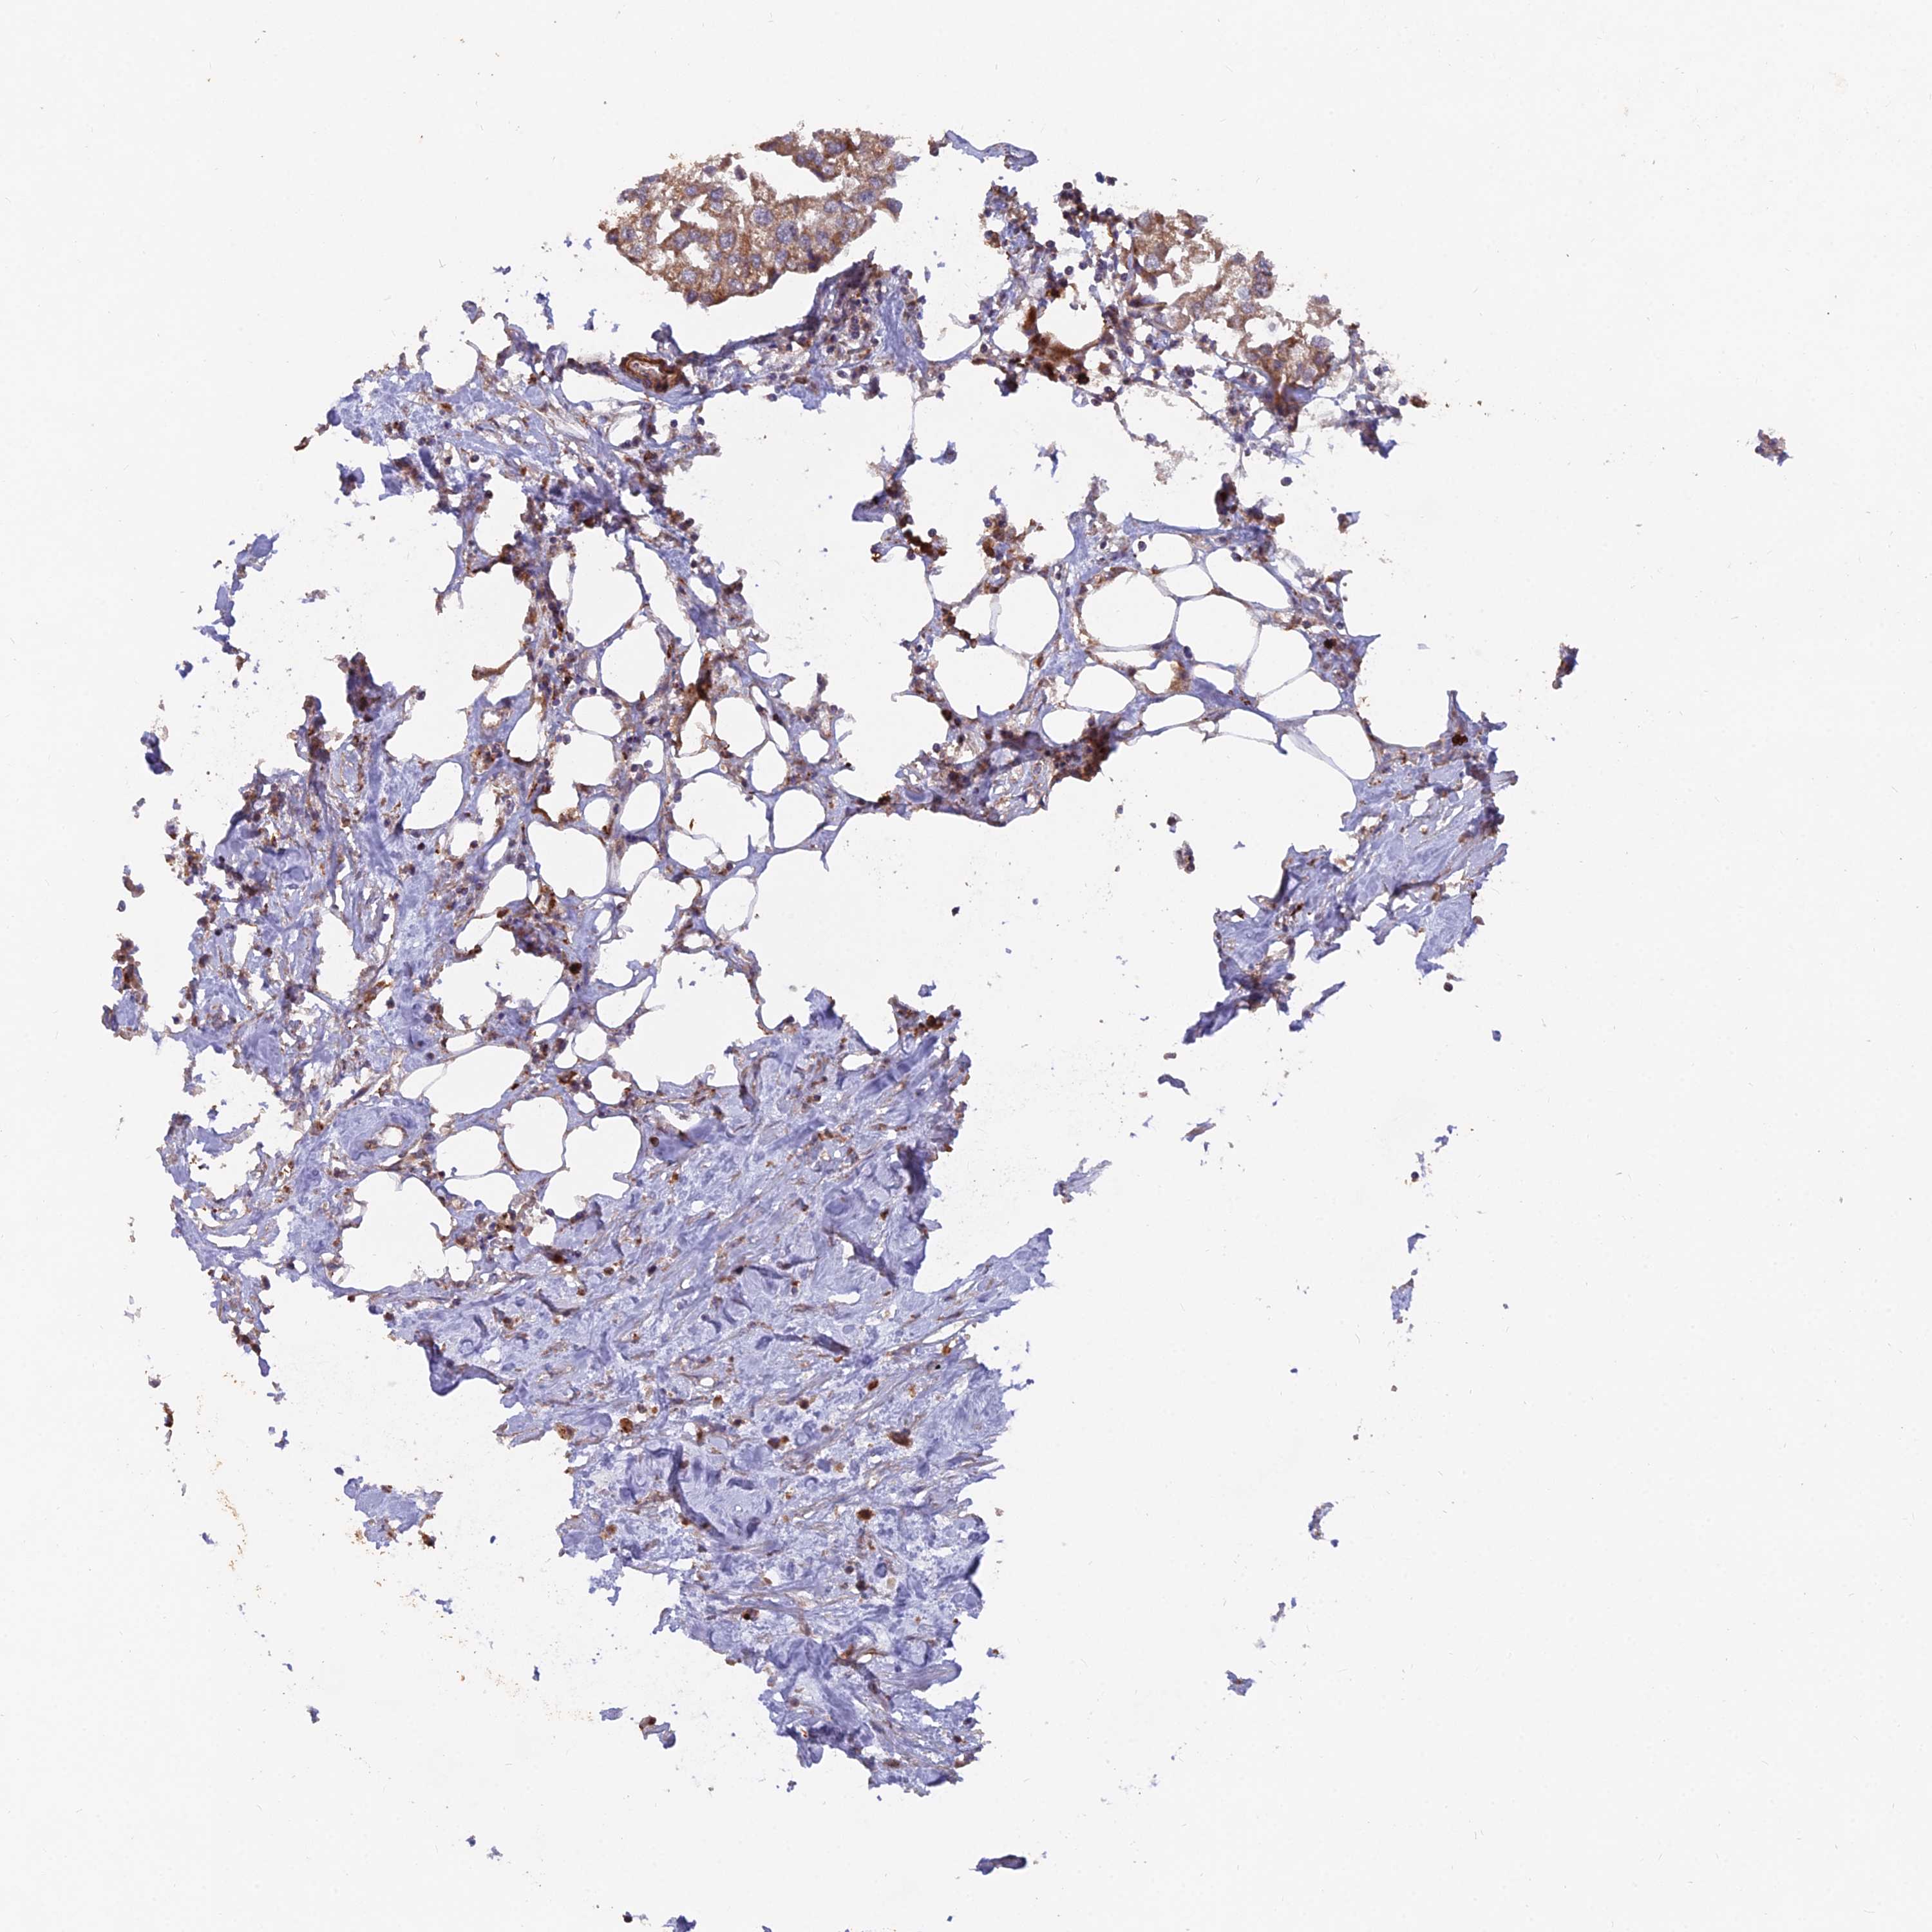

UROTHELIAL CANCER - Protein expressioni

A mouse-over function shows sample information and annotation data. Click on an image to view it in a full screen mode. Samples can be filtered based on level of antibody staining by selecting one or several of the following categories: high, medium, low and not detected. The assay and annotation is described here.

Note that samples used for immunohistochemistry by the Human Protein Atlas do not correspond to samples in the TCGA dataset.

Antibody stainingi

Antibody staining in the annotated cell types in the current human tissue is reported as not detected, low, medium, or high, based on conventional immunohistochemistry profiling in selected tissues. This score is based on the combination of the staining intensity and fraction of stained cells.

Each image is clickable and will lead to virtual microscopy that enables deeper exploration of all samples and also displays staining intensity scores, fraction scores and subcellular localization as well as patient and tissue information for each sample.

Antibody HPA042930

Staining

High

Medium

Low

Not detected

Intensity

Strong

Moderate

Weak

Negative

Quantity

>75%

75%-25%

<25%

None

Location

Nuclear

Cytoplasmic/membranous

Cytoplasmic/membranous,nuclear

Urothelial carcinoma, High grade

Urothelial carcinoma, Low grade